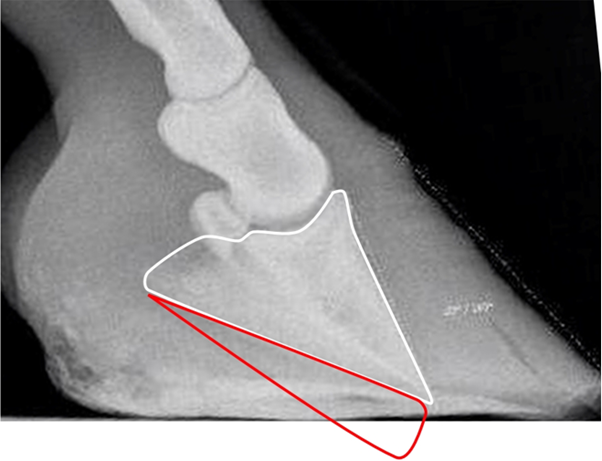

If the coffin bone was originally parallel to the toe wall, as the white marking suggests, and then “rotated” down to what the radiograph shows, where did all the materia in the red triangle go?

There is never any void inside the hoof where this missing tissue, or the coffin bone, could go. But the missing tissue must have gone somewhere, or?

The answer is that it didn’t go anywhere because the bone has not moved. It was never up by the hoof wall; the hoof wall was down by the coffin bone, and got pressed up by ground pressure after suffering laminitis.

The red line indicates the alleged original angle of the coffin bone.

The green line indicates the current angle of the coffin bone.

The yellow arrow points to pristine sole corium.